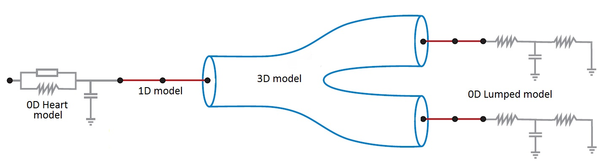

Boundary conditions from multiscale modeling of circulation: Another approach to impose the boundary conditions is to use reduced models, as 1D model or 0D (lumped) models. 1D and 0D models are mathematical models able to reproduce the systemic and pulmonary circulation. Figure 10 shows a standard approach to provide realistic local boundary conditions for 3D CFD simulations at the specific arterial domain using 1D models of the entire arterial tree and 0D models at the distal ends[83]. 1D model solves the Navier-Stokes equations under some assumptions (see appendix 9) and lumped models (0D models) can be derived from electrical circuit analogies where blood flow is represented by the current and arterial pressure by the voltage. Usually the electrical components of these circuits are resistances, inductances and capacitors. Where resistances represent arterial and peripheral resistance that occur as a result of viscous dissipation inside the vessels, capacitors represent volume compliance of the vessels that allows them to store large amounts of blood, and inductors represent inertia of the blood[75]. The values of these electrical components can be estimated from physical data of the subject [84][85]. This approach is quite used because it is capable to account for the effect of local pathological conditions on the whole circulatory system, providing realistic boundary conditions for the 3D problem [75][79][86].

|

| Figure 10: Coupling of 0D heart model, with 1D model (Systemic Circulation), 3D model (patient-specific geometry) and 0D lumped models (terminal resistance) to perform a computational analysis |